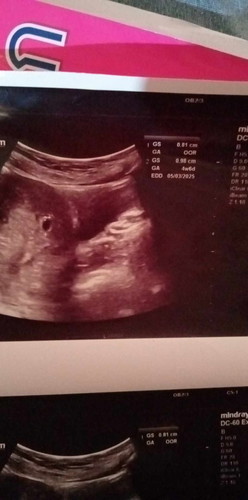

เรานับอายุครรภ์จากแผ่นอันตราซาวมั่ยค่ะในกรณีจำประจำเดือนไม่ได้ แล้วกีวีคจะเจอตัวอ่อนค่ะ ซาววันนี้4+6เจอแต่ถุงตั้งครรภ์#ขอบคุณล่วงหน้าสำหรับความคิดเห็นค่ะ #ขอบคุณล่วงหน้าสำหรับความคิดเห็นค่ะ #

บ้านนี้ ซาวด์ฝากครรภ์ครั้งแรกตอน 7วีค+4 เจอถุงไข่แดงยังไม่เจอน้อง มาเจอตอน 11วีค+3 ค่ะน้องมีแขนขาหัวใจเต้นแล้วตรงตาม ปจด ค่ะ ตอนนี้ 26วีค+6 แล้ว ของคุณแม่อายุครรภ์ยังน้อยอย่าเครียดนะคะ เดี๋ยวก็เจอน้องค่ะ☺️✌️🥰

ถ้าจำวันมาปจด.ไม่ได้ ยึดตามใบ อัลตร้าซาวด์เลยจ้า ไม่เป็นไร เพราะบางคนปจด.มาไม่ตรงกันอยู่แล้วแต่ละเดือน

บ้านนี้ก็จำ ปจด ไม่ได้ค่ะ นับตามอัลตร้าซาวด์ค่ะ น่าจะสัก 8 สัปดาห์น่าจะเห็นตัวอ่อนแน่ๆค่ะ

น้องยังเล็กมากๆค่ะแม่รออายุครรภ์มากกว่านี้ถึงจะเจอน้องค่ะแม่ไม่ต้องกังวลนะคะ🥰

บ้านนี้รู้ตอน4วีคเหมือนกันค่ะ เจอถุงตั้งครรภ์ มาเจอตัวตอน8วีค ตอนนี้20วีคละค่ะ